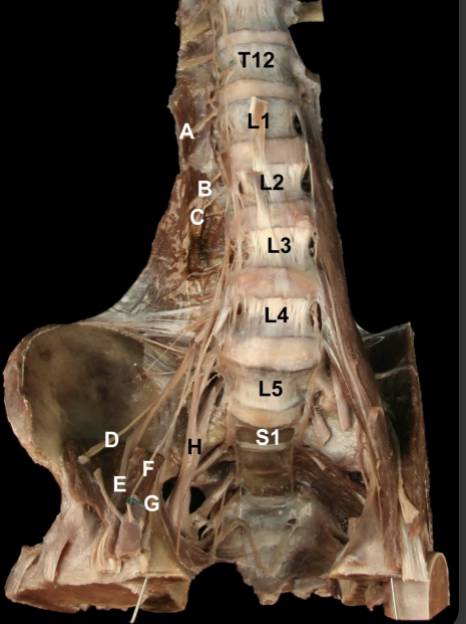

<p>Try and Identify the nerves and nerve roots of he <strong>Lumbarsacral Plexus&nbsp;</strong></p>

Try and Identify the nerves and nerve roots of he Lumbarsacral Plexus

A: Iliohypogastric n (L1)

B: Ilioinguinal n. (L1)

C: Lateral Cutaneous n. of the Thigh (L2-L3)

D: Femoral n. (L1-L4).

E: Geniofemoral n. (L1-L2)

F: Obturator n. (L2-L4)

G: Lumbosacral trunk (L4-L5)

H: Sciatic n. (L4-S3)

I: Genitofemoral n. (L1-L2).